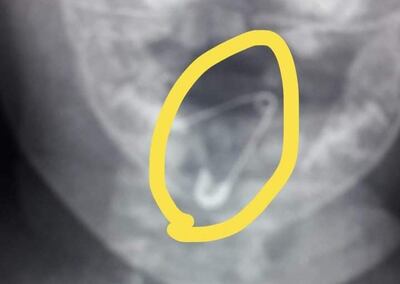

El hecho ocurrió en la noche del sábado. Aproximadamente a las 20:00 la madre, con su beba en brazos, llegó desesperada a la sección de Urgencias del Hospital Regional de Coronel Oviedo, porque su hija presentaba serios problemas para respirar y ante la posibilidad de haber tragado un objeto desconocido. Realizaron una radiografía y encontraron que un prendedor abierto estaba alojado en la garganta de la beba.

La doctora Yéssica Vargas dijo que la situación era muy grave, en vista de que el prendedor estaba abierto. Explicó que si el objeto hubiera pasado a las vías digestivas podría haber causado serias heridas internas que, a la vez, generarían sangrados que pondrían en peligro la vida de la beba de 8 meses.